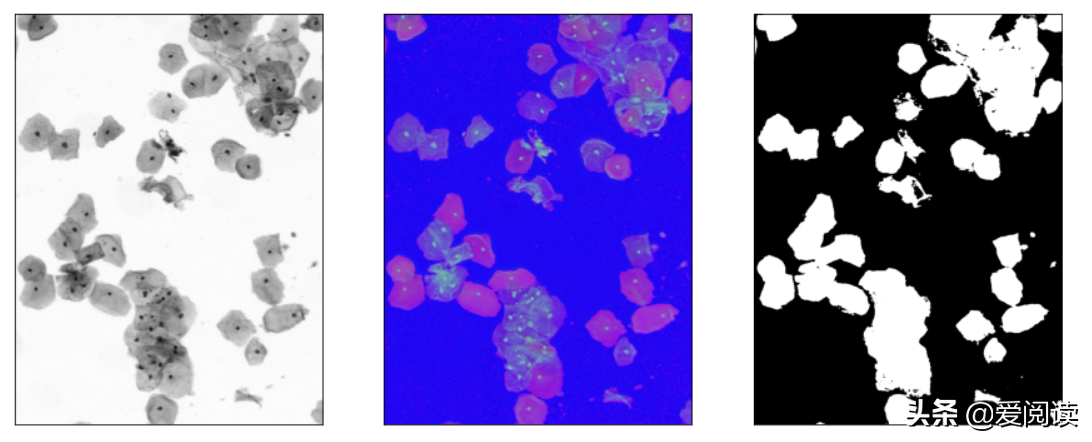

最终细胞核分割定位效果:左边是原图,右边是细胞核行为结果:

例子1:

你试过吗?图像(细胞)分割

例子2:

可以看到效果很得不错的。当然这里面还有很大的优化空间。

左边为原始灰度图像, 右侧为g通道图像,由于图像本身的特征,我们选择g通道进行处理。

效果如下:

可以看到方法2明显要比方法1好很多。